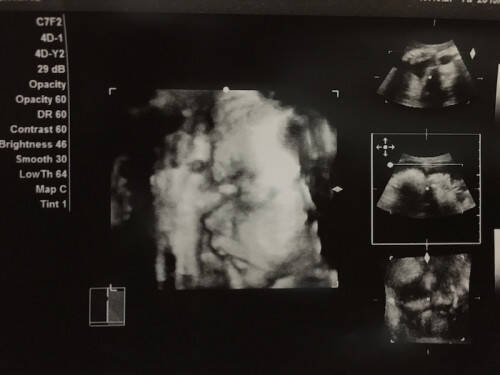

性別判断お願いします!エコー写真あり💓 12週のエコーをr先生に送りました! 動画が長かったので後半部分を1回目送ったら 6〜7割女児と言われました! でもやっぱりフル動画送ろう!と思って2回目送ったら 6割男児と言わSep 03, 17 · 18週1日(18w1d・性別不明)|ぴーさよ さん(30歳) エコー写真撮影時のエピソード: 初めての4Dエコーでした。 いつも見てるエコーとは違い立体的に見えて愛しさが増しました(^^) 他の人がこれを見たらただのホラー写真ですが。先生にエコー写真を見て性別判定していただくスレです。 :(火) IDCFkjx >>963 4Dの横断像ですが、陰茎の可能性が極めて強いと思います。 >>965 男児確定します。 15週のエコーです

Apr 23, 12 · 12週2日の4Dエコーです。明日で週を迎える妊婦です!まだ性別が分かっていないのですが、12週の4D写真で、オマタがきれいに写りました。この時 期は女の子でも突起物があるみたいですが、調べると女の子の突起物は下向き、男の子は前向きにあるみたいで、この写真を見る限りFeb 18, · エコー写真を妊娠の経過別に紹介! 見方や性別の見分け方 妊娠中の超音波検査でエコー写真をもらうことがあるでしょう。 エコー写真は赤ちゃんの様子を確認することができますし、いつまでも保管していきたいものですよね。 妊娠週以降になると

Baby 妊婦健診 12週4日 初めての4d超音波診断 毎日happy わが家の成長日記 楽天ブログ